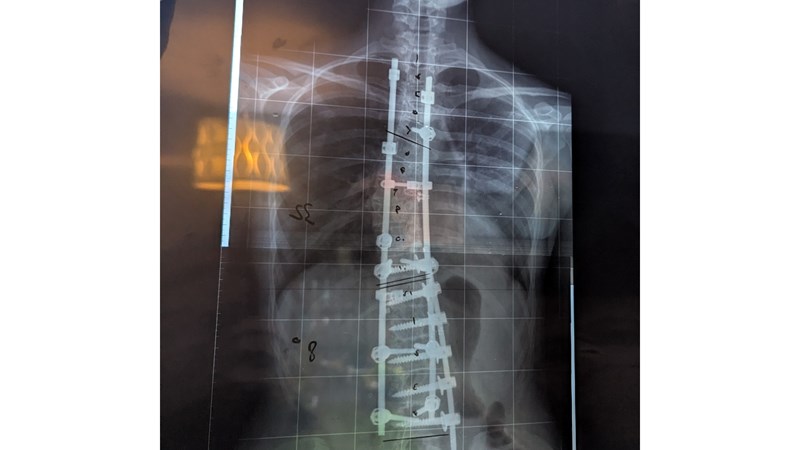

Together with my family, physios, teachers and surgeons we decided to delay surgery for as long as we could so that I could keep dancing- doing what I loved for as long as possible. Finally, I had two eight hour operations where my spine was straightened with Titanium rods and screws.